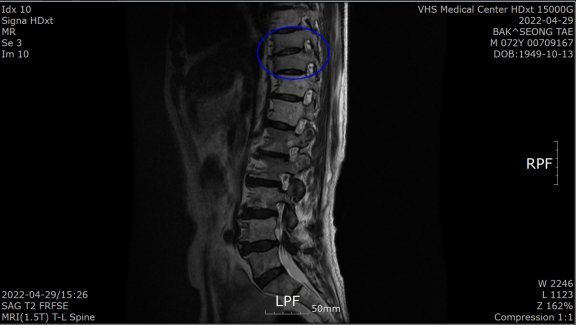

“1월 말 허리가 아파 병원에 갔더니 전립선암 말기라고 하더라고요. 전 베트남 참전용사로 국가유공자라 중앙보훈병원에서 진단 받았습니다. PSA(Prostate Specific Antigen·전립선 특이항원·전립선암의 선별검사 및 치료 판정을 위한 종양지표지자 검사)가 935 ng/mL라는 겁니다. PSA 4 ng/Ml 이하가 정상이라는데…. 너무 놀라서 그동안 아무 증상이 없었다고 했더니 전립선암은 증상이 없다 갑자기 나타난다고 하더군요. 전이가 돼 흉추 9, 10번이 시커멓게 썩었다고 하더군요. 참 나…. 방법이 죽을 방법 밖에 없다니. 하느님이 원망스러웠습니다.”

4월 29일 검사에서 PSA 수치가 0.059ng/mL로 떨어진 것이다. 그는 “MRI(자기공명촬영) 결과 새까맣던 흉추도 하얗게 정상으로 돌아왔다”고 했다. 말기암 판정 5개월여 뒤인 7월 29일 검사에선 PSA가 0.008 ng/mL로 떨어져 있었다.